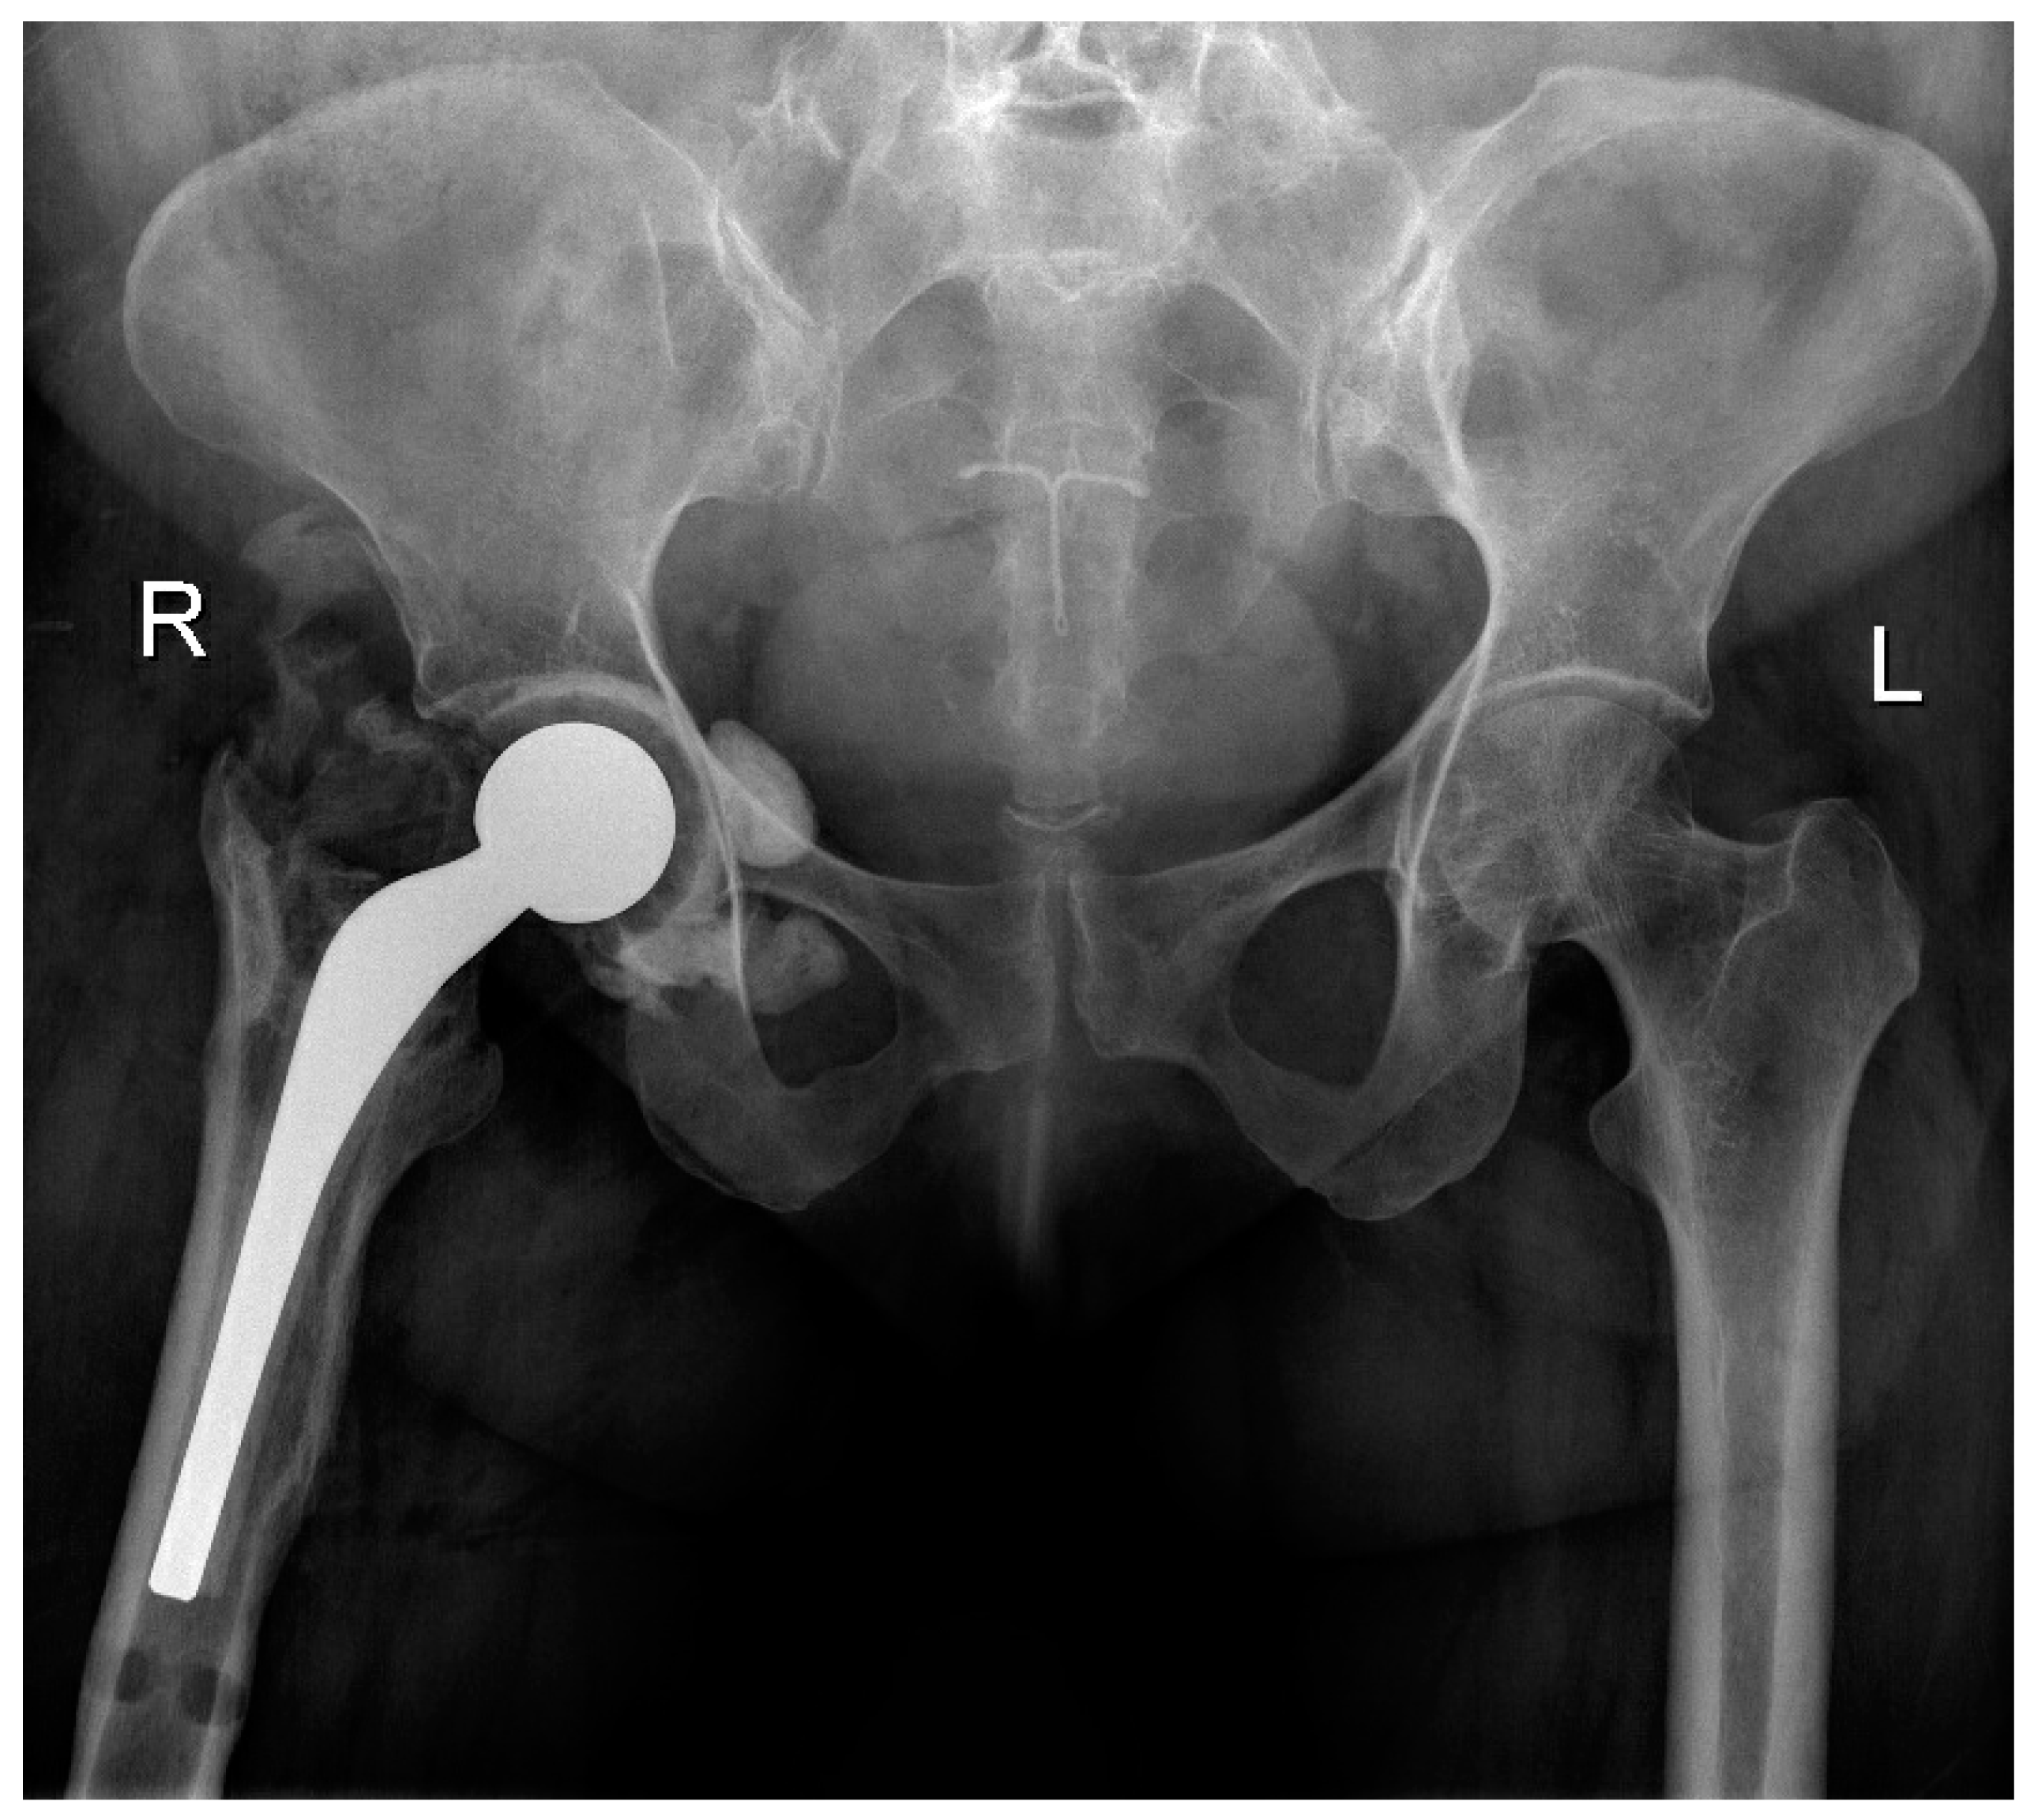

5.1. Surgical Technique

| Conversion to THA | 4 (44%) | 1 (20%) | 3 (75%) | 0.206 |

| THA requiring revision | 3/4 (75%) | 1/4 (25%) | 2/4 (50%) | 1.000 |